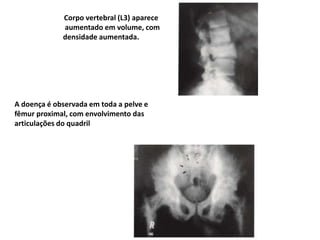

Corpo vertebral (L3) aparece

aumentado em volume, com

densidade aumentada.

A doença é observada em toda a pelve e

fêmur proximal, com envolvimento das

articulações do quadril